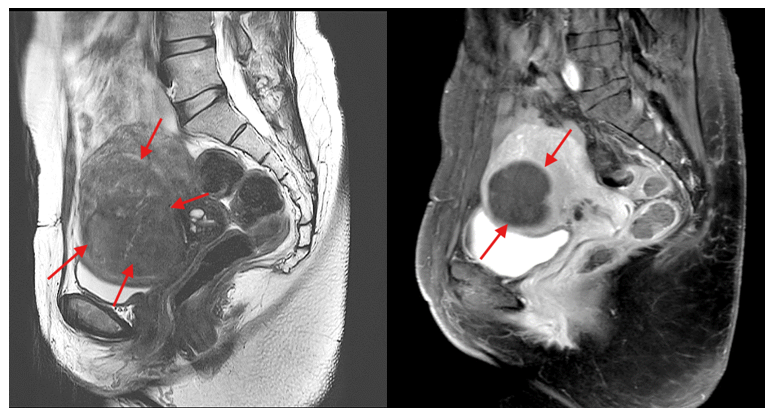

45 year old female with heavy period, anaemia with severe pain from extensive uterine adenomyosis. UAE was done after 2 injections of hormone (GnRH agonist). The MRI image on the left showed gross diffuse darkening of uterine tissue (left) from the tumor invasion. The image on the right 1 year after UAE showed complete shrinkage of the adenomyosis with an avascular scar (right). She achieved complete symptomatic relieve and enjoys a great life post UAE.